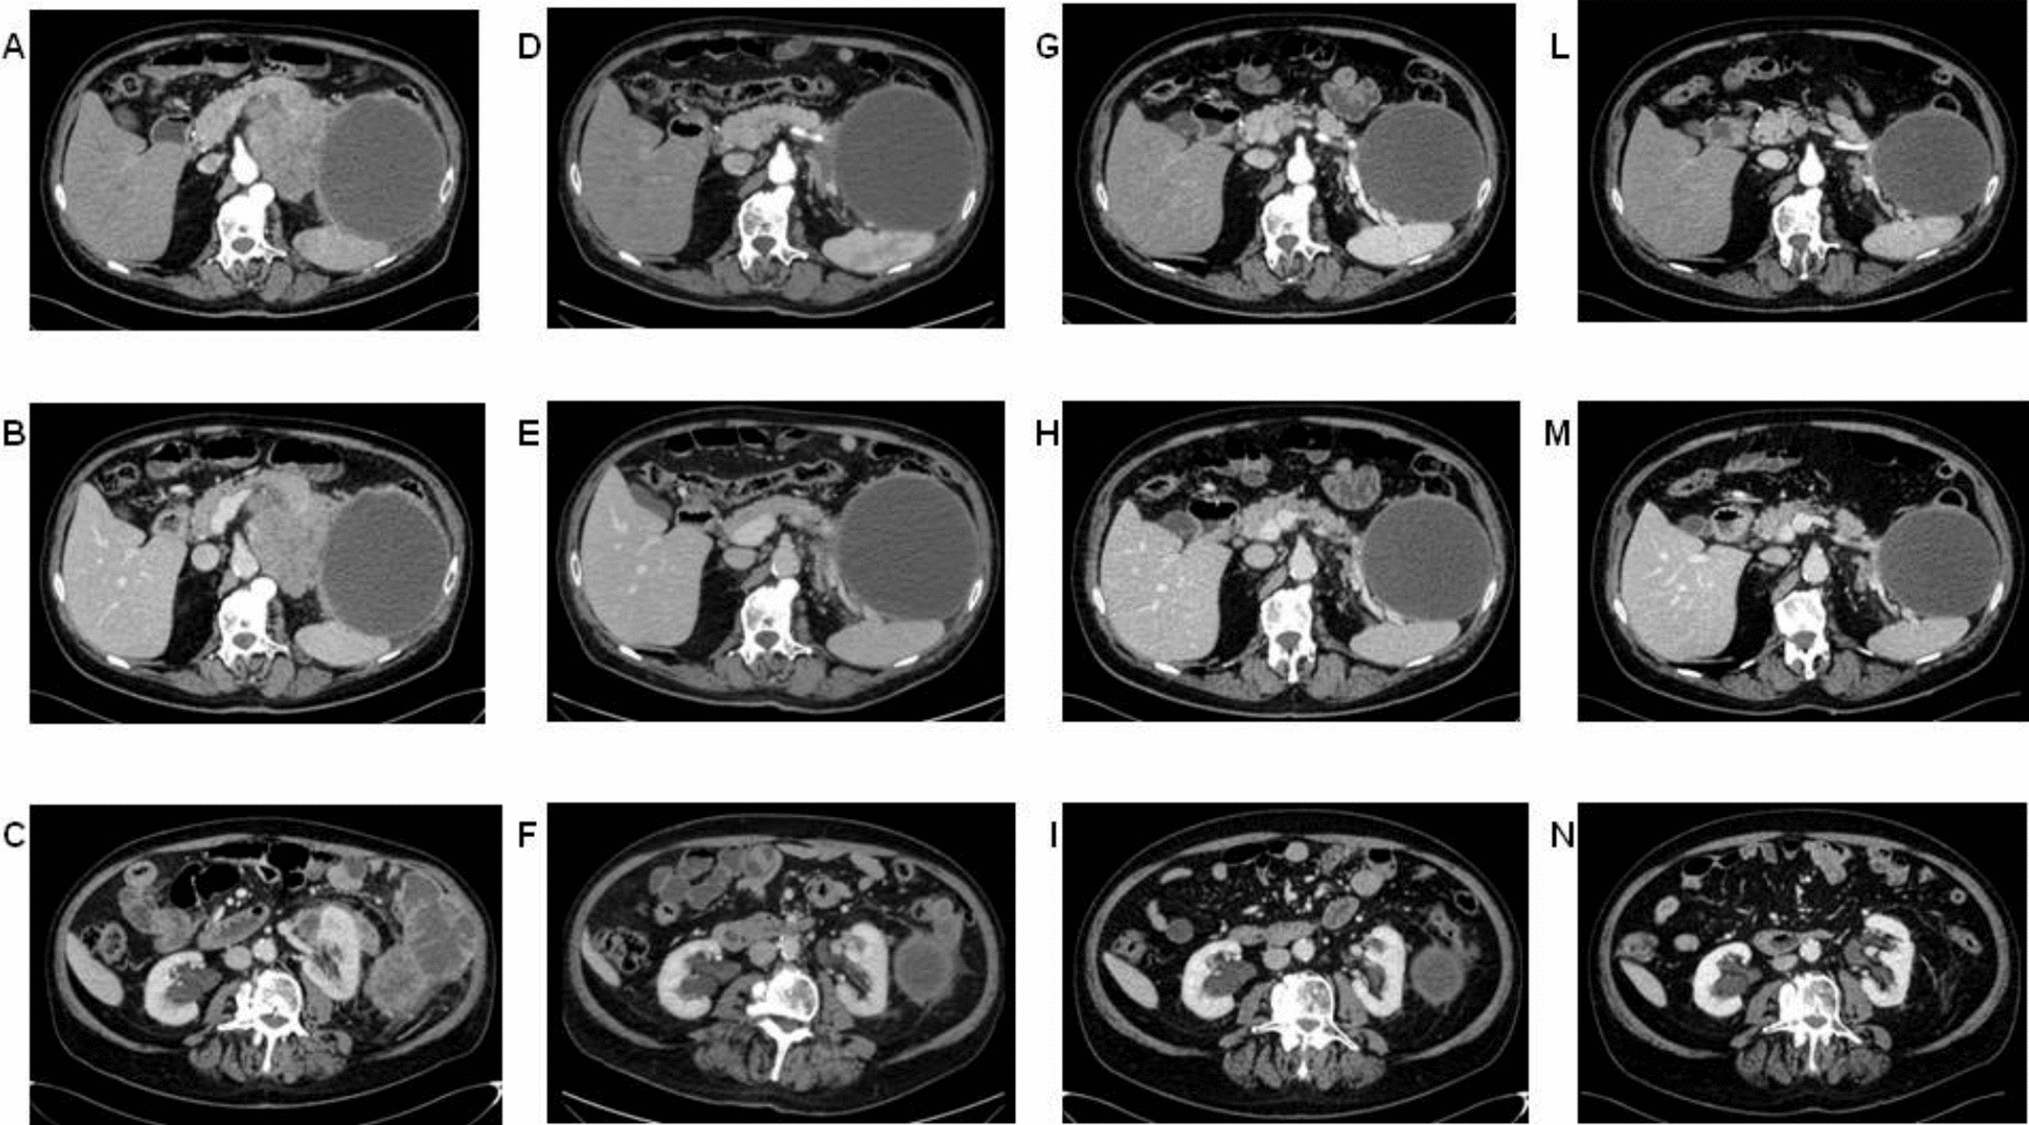

Computed tomography (CT) revealed confluent masses with a central hypodense component, occupying an area of 15 cm in the pancreatic tail. This lesion appeared not dissociable from the ascending colon, bordered the large gastric curvature, the left adrenal gland, the spleen and the abdominal wall (Fig. 1A). Gross locoregional lymphadenopathies were shown. Fluorodeoxyglucose (FDG)-positron emission tomography (PET) confirmed an extensive hypermetabolic infiltrating neoplastic mass, with locoregional lymph nodal metastases (Fig. 1B). The patient underwent endoscopic ultrasonography with fine-needle aspiration (EUS-FNA). The cytological examination revealed the diagnosis of pancreatic acinar adenocarcinoma, supported by immunohistochemical positivity for BCL-10 and negativity for chromogranin A and synaptophysin (Fig. 2A–D). CEA resulted over the upper limit, while CA-19.9 and AFP showed normal levels.

Fig. 1

CT (A) and PET (B) scans at baseline

Fig. 3

CT scans after two lines of chemotherapy, before the start of pembrolizumab (A, B, C). CT scans after 3 months (D, E, F), after 6 months (G, H, I) and after 10 months (L, M, N) of pembrolizumab